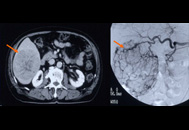

- 画像診断:腹部超音波検査(エコー検査)、CT/MRI、血管造影(カテーテル検査)

肝臓がんのカテーテル検査

肝臓がんは血流豊富ながんである